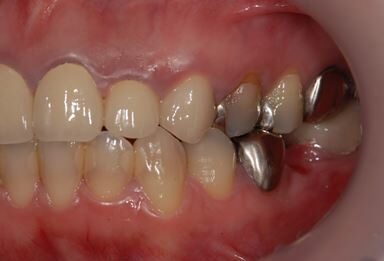

インプラントの症例写真 IMPLANT

インプラント治療

| 性別/年齢 | 女性 / 34歳 | ||||||||||||||||||||||||||||||||

| 治療方針 | 右下奥欠損部分をインプラント治療にて機能的・審美的回復を行う。 | ||||||||||||||||||||||||||||||||

| 治療内容 | インプラント1本、メタルボンドセラミッククラウン1本 | ||||||||||||||||||||||||||||||||

| 総治療費 | 252,000円 | ||||||||||||||||||||||||||||||||

| 治療期間 | 4ヶ月 |